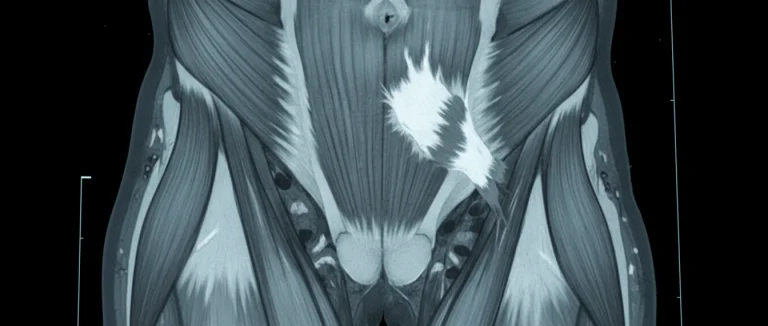

Магнитно-резонансная томография (МРТ)

МРТ считается золотым стандартом для подтверждения разрыва мышцы. Он предоставляет детализированное изображение мягких тканей, позволяя точно определить размер и локализацию разрыва, а также оценить состояние окружающих структур.

Врач начинает с осмотра: оценивает локализацию боли, отёк, гематомы и диапазон движений. УЗИ позволяет быстро увидеть разрыв сухожилия и степень отёка, удобно для динамического контроля. Магнитно-резонансная томография (МРТ) считается золотым стандартом – даёт детальное изображение мягких тканей, точно определяя размер и локализацию разрыва. При необходимости могут применяться КТ для оценки костных структур или электромиография (ЭМГ) для проверки нервно‑мышечного взаимодействия.